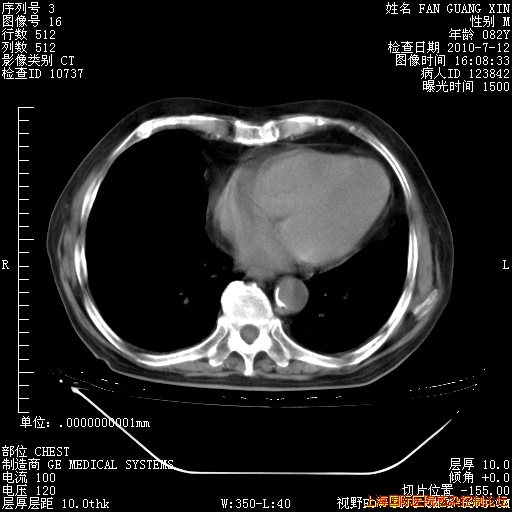

今天复查CT

今天CT

整整相隔30天的肺部CT好像有所好转啊。甲强龙减量第3天,需要观察体温。

海管,自昨日你和我通完话后,不知您岳父消化道症状有无缓解?体温怎样?阅读7.12日胸部ct,个人认为目前激素治疗是有效的,甲强龙减量是适宜的。因在抗痨治疗,需密切观察肝功、肾功能和血常规。不过,老年、长期住院和大量使用激素,很担心菌群失调发生